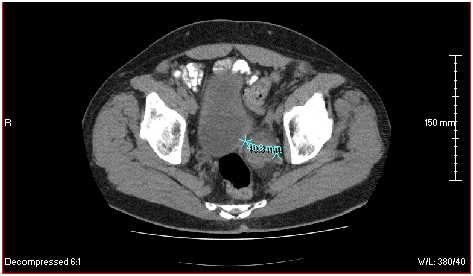

The patient is a 63 year-old male diagnosed in February 2010 with transitional cell bladder carcinoma located at the left posterior ureterovesical junction. The initial CT scan showed the tumor measured 3.91 cm in its posterior to anterior diameter (Figure 2). A plant-derived extract called Salicinium, which is thought to be selectively toxic for cancer cells, was prescribed by his physician. By 3 months, however, the tumor had grown to approximately 7 cm x 4 cm, with compression of the bladder wall (Figure 3). The patient’s physician then decided to try intravenous Enercel. The patient gained symptomatic relief and over the next 2 weeks reported passing blood and tissue pieces in his urine. After 12 weeks of Enercel therapy the tumor had decreased back to 4.01 cm in its widest diameter and was no longer compressing the bladder (Figure 4). The volume of the tumor since beginning of the Enercel therapy was estimated to have decreased by 53%. Hypodense areas were seen inside and along the edges of the mass consistent with tumor cell necrosis. Symptomatically, the patient reported feeling much improved in his overall health. Rather than continuing with Enercel, the patient opted to travel to Mexico for stem cells, catheter administration of supplements and attempted catheter removal of residual tumor. These endeavors led to Pseudomonas aeruginosa sepsis that failed to respond to months of antibiotic therapy. Surgery was finally attempted but failed and the patient died. The case is informative, however by the Enercel induced a significant reduction in tumor size (7 cm versus 4 cm largest diameter) and the clinical and radiological evidence of apparent tumor necrosis.

Figure 3 A CT scan of the pelvis of the same patient obtained on 5-18-2010. The radiologically defined tumor had grown, such that its widest diameter was now approximately 7 cm. The tumor was compressing the patient’s bladder. The Salicinium was discontinued and the patient was begun on Enercel.